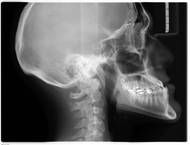

Byla to děsivá fotografie. Ruka kostlivce, ozdobená prstenem, jako z nějakého hororu o upírech. Ideální ilustrace do románu pana Brama Stokera, který vyšel teprve nedávno. Tento kostlivec je však živý až moc. Dáma kypící zdravím hledí udiveně na obrázek. Neviditelné paprsky X si našly cestu a odhalily poprvé tajemství lidského těla.